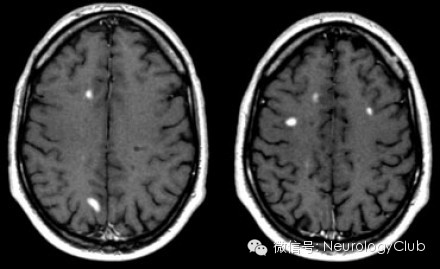

第二方面:T1像上显示的黑洞black holes)

1、代表脑实质局灶损伤区域

2、可能反映急性水肿性病变或基质破坏伴轴索丢失

3、一般不强化;水肿性黑洞起初强化,时间久后不强化